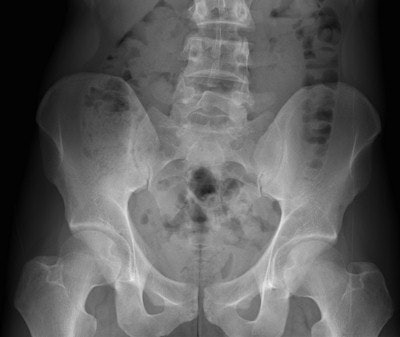

Residual cocaine-filled packet found in the cecum of a 33-year-old body packer. Abominal x-ray of the lower abdomen (above) shows no clear abnormality, whereas sagittal CT reformatted image (below) clearly depicts a dense packet (arrow), located in the cecum. Note that even in retrospect, the packet is still not visible on AXR. All images courtesy of Dr. Pascal Rousset.